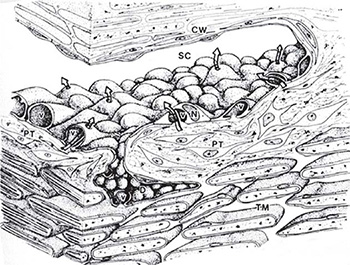

Giant vacuoles, probably formed by invagination of the basal plasmalemma, are a prominent feature of the inner wall of Schlemm's canal (Figure 1.4). They provide access for aqueous humor in the pericanalicular region,19 and some also communicate with Schlemm's canal through an apical opening, thus forming a transcellular channel.20 Red blood cells can pass through these channels due to their deformability, but macrophages, red cell ghosts and sickled red cells become trapped in the inner portion of the meshwork. Some vacuoles have openings on the inner and outer sides, so they can be considered transcellular microchannels. Some authors have assumed that these structures provide a valvular function, because the openings on the meshwork side are often larger than those on the luminal side and because their apical pores are usually not located directly opposite the basal openings (Figure 1.5).21

FIGURE 1.4: A composite three-dimensional schematic rendering of the walls of Schlemm's canal (SC) and the adjacent trabecular meshwork (TM). The spindle-shaped endothelial cells lining the trabecular wall of Schlemm's canal are characterized by luminal bulges corresponding to unique macrovacuolar configurations (v) and nuclei (N). The macrovacuolar configurations are formed by surface invaginations on the basal aspect of individual cells which gradually enlarge to open eventually on the apical aspect of the cell surface thus forming transcellular channels (arrows) for the bulk flow of aqueous humor down a pressure gradient. Pericanalicular tissue (PT). Corneoscleral wall (CW).(From Tripathi RC and Tripathi BJ in Duane TA and Jaeger EW (eds) (1982) Biomedical Foundations of Ophthalmology, Vol. 1, published by Harper and Row)

The formation of the vacuoles seems to be pressure dependant, the number and size being decreased at low pressures and reversed at high pressures.22 The transcellular route is responsible for most of the aqueous entering Schlemm's canal, and only about 1 percent of the inner wall conductance can be attributed to the non-vacuolar channels.23